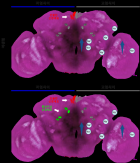

The two studies examined how participants accepted these sounds and used electroencephalogram (EEG) tests to confirm that the brain still recognized the 40Hz stimulation even when hidden within a natural soundscape. The results showed that the redesigned sounds were significantly easier to listen to over long periods while successfully triggering the intended brainwave responses.

Title: EEG-based Verification of Soundscape-mediated 40Hz Gamma-band Stimulation